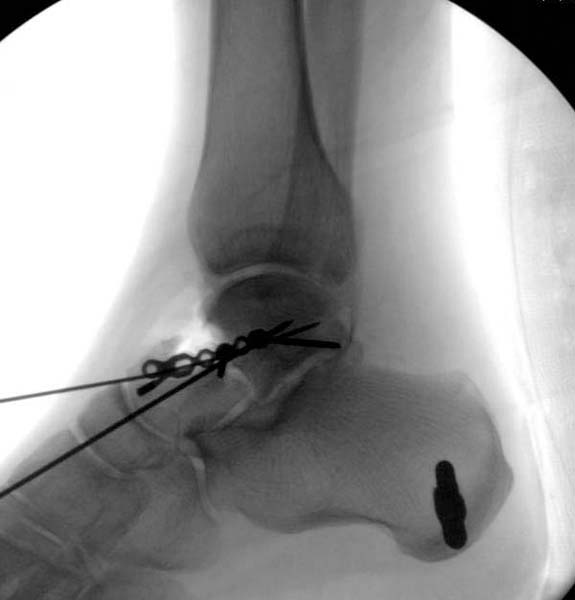

Больная стабильная после хирургических мероприятии и получив добро, приступили к закрытому вправлению таранной кости с укладкой наружного фиксатора. Затем укладка больную на бок и открытый остеосинтез перелома-вывиха головки бедра.

После спадения отека на стопе произведена фиксация тарана. Кстати, коллеги пересмотрели первоначальную консультацию по позвоночнику и на двух уровнях провели фиксацию. Из-за длительного постельного режима без нагрузки таз не стали оперировать...